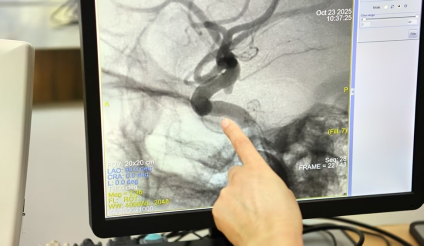

清晨七点,当大多数人还在通勤路上或享用早餐时,刘俊教授已端坐办公桌前,仔细研究着当天手术患者的CT影像。笔记本上密密麻麻标注着出血位置、血管走向,甚至连微小的钙化点都被特殊标记。

神经外科被誉为“医学金字塔的塔尖”,毫厘之差便是生与死的距离。脑动脉瘤之所以被称为“颅内定时炸弹”,是因为其壁薄如纸、形态不规则,在血流冲击下随时可能破裂。刘俊指出:“脑动脉瘤并非真正意义上的肿瘤,而是脑血管局部异常扩张形成的‘气泡’,一旦破裂出血,死亡率高达30%以上”。

面对这样的“定时炸弹”,刘俊开展了5000余例脑动脉瘤手术。他创新性地应用复合手术再通术式,使动脉瘤夹闭术的成功率大幅提升。在手术中,刘俊手持器械在毫米级的空间内操作,汗水顺着额角滑落却不让手有半分颤抖。他凭借精湛技艺实现了高达96%的治愈率。